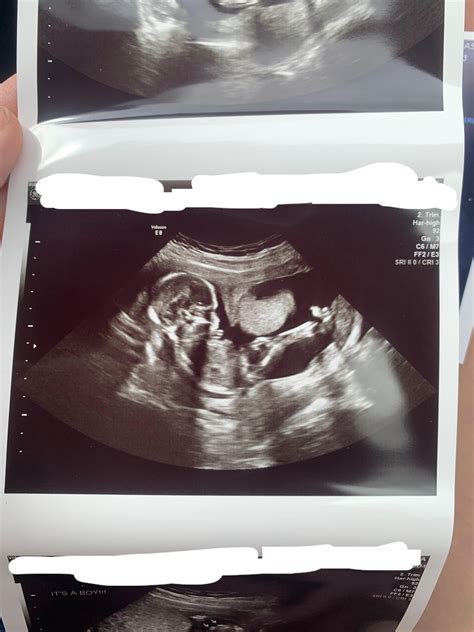

• Ultrasound Monitoring: Regular ultrasounds can help track the fetus's growth and development, as well as assess the uterine environment.

Despite these challenges, many women with a bicornuate uterus can have successful pregnancies with proper medical care and monitoring.